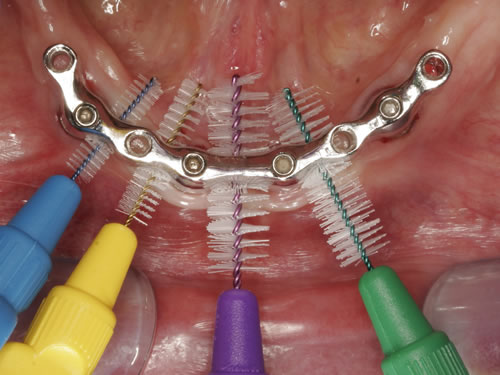

Zusätzlich müssen aber die Pfeiler zwischen den Zahnkronen oder den Stegelementen gesäubert werden. Dazu sind kleine Bürstchen geeignet, die von außen und innen zwischen den Zähnen und Implantaten hindurchgeführt werden (Abb. 9.6 bis 9.9).

Abb. 9.7: Reinigung mit einem Zahnzwischenraumbürsten.

Abb. 9.8: Reinigung mit verschiedenen Zahnzwischenraumbürsten.

Abb. 9.9: Zahnzwischenraumbürsten mit langem Handgriff für die hinteren Zähne.

Diese Bürsten werden als Zahnzwischenraumbürsten oder Interdentalbürsten bezeichnet; sie sind Einmalartikel oder mit austauschbaren Ansätzen erhältlich. Sie können natürlich nur dann eingesetzt werden, wenn die Kronen und Brücken so gearbeitet wurden, dass ein genügend großer Zwischenraum vorhanden ist.